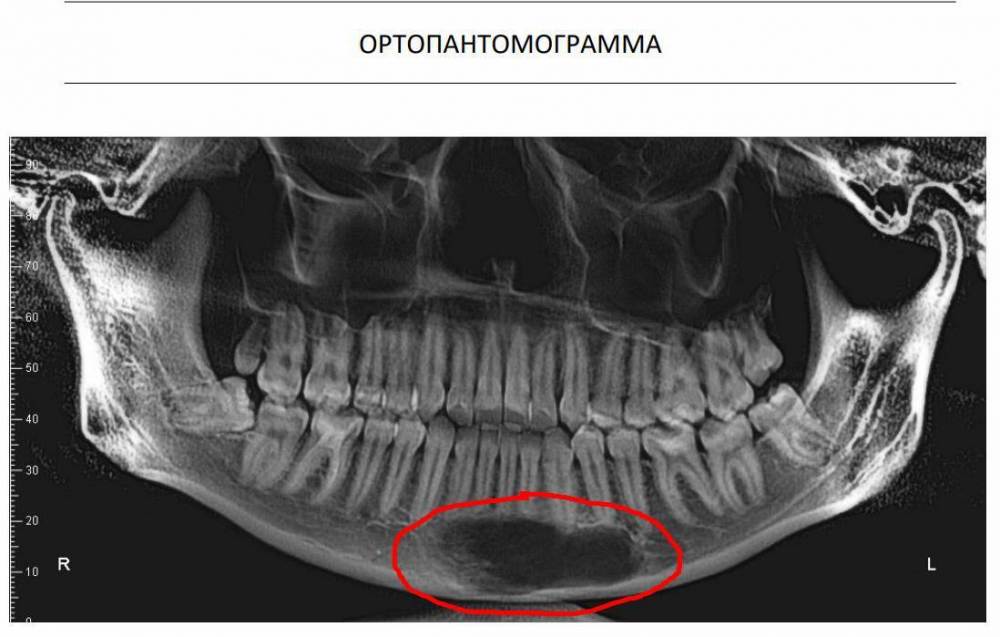

domka Опубликовано 8 июля, 2023 Поделиться Опубликовано 8 июля, 2023 Добрый день. Сделали кт снимок перед установкой брекет-системы. Заметили на снимке на нижней челюсти под зубами темное пятно (затемнение) на несколько зубов. Установка отложилась, но внятного ответа, что это может быть не получила. Подскажите, что это такое может быть и насколько серьезна проблема, если она есть? Ссылка на комментарий

АнтонТЛТ Опубликовано 8 июля, 2023 Поделиться Опубликовано 8 июля, 2023 Нужно кт смотреть, а не ортопантомограмму. Может быть просто артефакт снимка, либо киста 1 3 Ссылка на комментарий